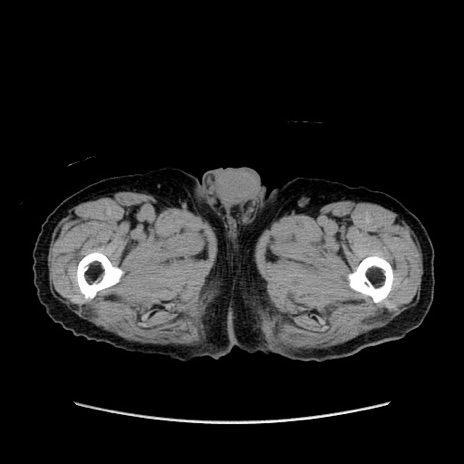

症例24(横断像)

【症例】80歳代男性

【主訴】左側腹部痛、嘔吐

【現病歴】本日早朝より左腹部に痛みあり。昼頃嘔吐認めたため、救急要請。

【既往歴】直腸癌(Mile手術)、胆摘

【身体所見】意識清明、BT 35.9℃、BP 221/93mmHg、SpO2 97%(RA) 、腹部:左ストーマ周囲に限局性の腹部膨隆あり。 膨隆部自発痛・圧痛あり・軟。

【データ】WBC 7700、CRP 0.09